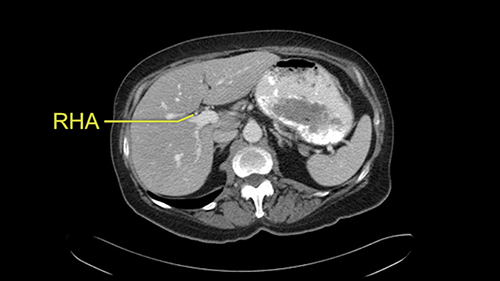

The procedure-specific slowing down moments from a technical point of view for a right hemihepatectomy include a careful evaluation of the inflow structures including the right hepatic artery, the right portal vein, as well to make sure that I have identified and preserved the left hepatic artery and the left portal vein at all times, and minimize any injury or dissection of the common bile duct. Also, I am careful when I mobilize the right liver, not to tear the right triangular ligament and cause bleeding of the liver as I mobilize it off the retroperitoneum and the bare area. In addition, the last procedure-specific slowing down moment is to carefully identify the right hepatic vein and ensure that I encircle it safely without damaging the IVC or the middle and left hepatic vein structures at all times.

So I would then focus on the hepatic outflow because that’s the way we do the operation is by mobilizing the liver. So the vena cava looks quite normal. The right hepatic vein looks quite normal. There are no large additional outflow veins from the right lobe which would generate slowing down moments. The hepatic artery is unremarkable and is not usually an issue we can define the anatomy quite clearly at surgery.

![[RHA]](jpg/preop_sg_moment3.jpg)